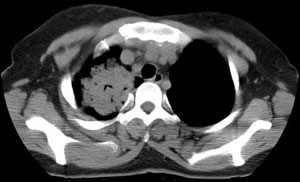

女性,30岁。

病史为胸痛20多天,无畏寒发热,无消瘦,无咳嗽咳痰。总之症状很逍遥。

临床以胸痛待查收住入院。

双肺野可见散在大小不等结节及肿块影,内密度不均匀,边缘部分清,部分欠清,纵隔未见明显肿大淋巴结.右侧胸腔少理积液.结合临床,考虑韦格肉芽肿可能吧,巨淋巴增生,结节病,特殊感染都要考虑.转移瘤临床不象.

本病例特点如下:

1.青年女性,以胸痛20多天就诊,无呼吸道及感染临床症状体征,无原发肿瘤病史;

2.肺ct表现为两肺多发大小不等结节影,大结节位于肺尖部,小结节多位于肺外带胸膜下,大结节内可见支气管充气征,周围可见月晕征(指在结节状或肉芽肿样病灶周围呈环形磨玻璃影),右肺门及腔静脉后可见小淋巴结,右侧胸腔内少量液体。

两肺散在分布大小不等的肿块及结节影,边缘毛糙,有分叶、毛刺,病灶密度不均匀,可见支气管充气相与空泡征。病变大多位于胸膜下,可见胸膜凹陷及胸腔积液。气管腔静脉间可见小结节影。